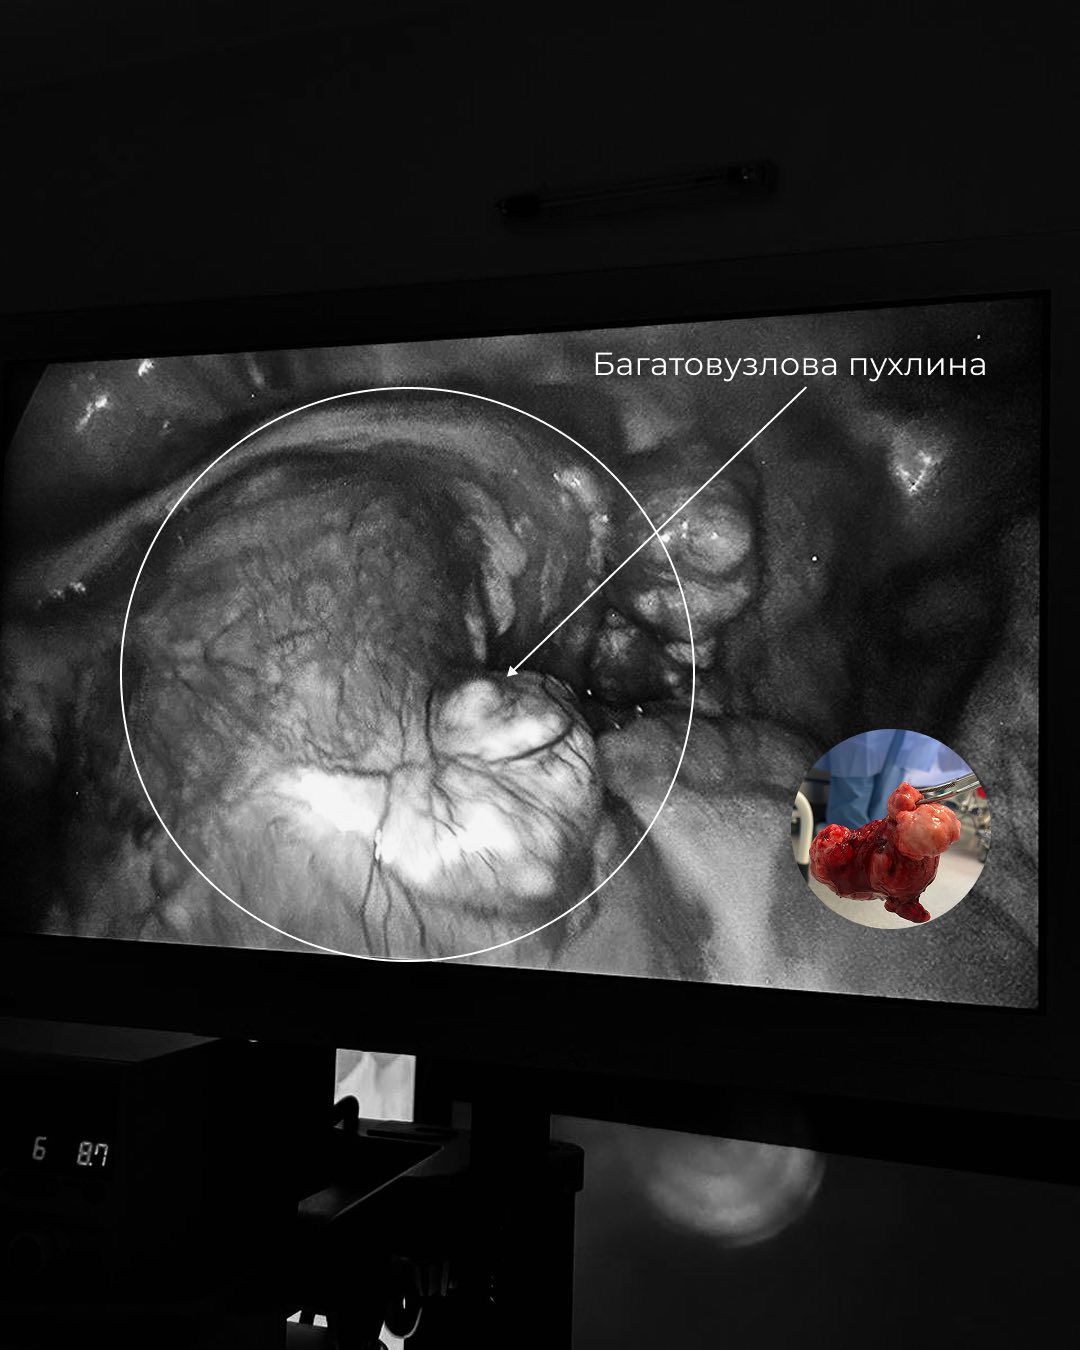

За результатами обстежень було вирішено провести операцію. Під час діагностичної лапароскопії лікарі виявили, що з рудименту матки утворилася пухлина, що нагадувала вузлову міому. Найбільший вузол досягав розміру 7-8 см, а поруч були й менші утворення. Оскільки пухлина могла спричинити больовий синдром, перекручування вузлів або навіть бути злоякісною, було ухвалене рішення про проведення операції.

«Такий випадок вкрай рідкісний. Подібний описувався в американській літературі лише один раз. Операція була надзвичайно складною. На неї зійшлося все відділення, адже подібного в нашій практиці ще не траплялося. Цей випадок унікальний не лише для нашої лікарні, а й для української хірургічної гінекології загалом», — каже Юлія Овечко, завідувачка гінекологічного відділення Лікарні Святого Пантелеймона.